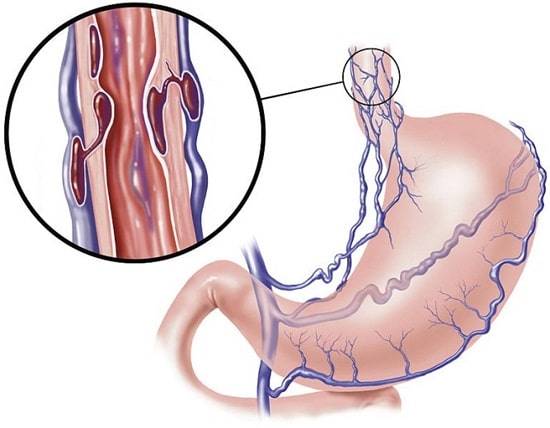

واریس مری، بزرگ شدن غیرطبیعی رگها در لولهای که گلو و معده(مری) را به یکدیگر متصل میکند، رخ میدهد. این مشکل اغلب در افرادی که بیماری شدید کبدی دارند رخ میدهد. واریس مری هنگامی بروز میکند که جریان طبیعی خون به کبد، توسط لخته خون یا بافت زخم در کبد، مسدود میشود. جهت دور زدن این انسداد، خون به رگهای کوچکتری که جهت انتقال این حجم از خون طراحی نشده است، جریان مییابد. خون از رگها نشت میکند یا حتی ممکن است دچار پارگی شود که منجر به خونریزی خطرناک می شود. تعداد زیادی از داروها و روشهای درمانی پزشکی میتواند خونریزی واریس مری را متوقف کرده یا از آن پیشگیری کند. در این مقاله، درباره علائم، علت، درمان و پیشگیری از واریس مری اطلاعاتی را دریافت خواهید کرد. باید بدانید که هر زمان بخواهید رگهای واریسی در ناحیه مری را درمان کنید، باید به یک متخصص باتجربه و ماهر مراجعه کنید که با روشهای درمانی و کنترل عوارض به خوبی آشنایی داشته باشد. این کار خطرات و عوارض جانبی و همچنین زمان بهبودی درمان را کاهش میدهد.

فشار بالای خون در سیاهرگ، (فشار بالای سیاهرگی) خون را به رگهای خونی اطراف پمپاژ میکند که شامل رگهای درون مری میباشد. این رگهای خونی دیواره نازکی دارند و به سطح نزدیک هستند. خون اضافی باعث میشود که آنها بزرگتر شده و متورم شوند. همچنین واریس ممکن است در رگهای خونی کوچک در بخش فوقانی معده ایجاد شود.

اگر فشار ناشی از افزایش خون بالا رود، واریس پاره شده و خونریزی ایجاد میکند. خونریزی یک وضعیت اورژانسی است که نیاز به درمان فوری دارد. خونریزی غیرقابل کنترل میتواند به سرعت منجر به شوک و مرگ شود. همچنین ترومبوز ( لخته خون) در سیاهرگ یا رگ طحال که به سیاهرگ متصل است میتواند باعث ایجاد واریس مری شود.